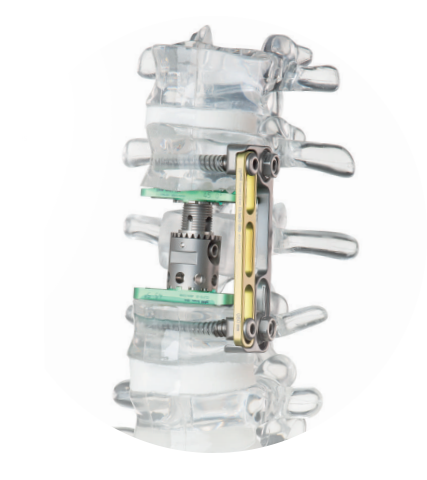

Para lidar com a dor crônica na coluna, é essencial adotar uma abordagem abrangente, que inclua técnicas cirúrgicas avançadas, intervenções minimamente invasivas e uma equipe multidisciplinar dedicada ao manejo da dor. Aliviando a dor crônica na coluna, não apenas melhoramos a função física, mas também elevamos a qualidade de vida dos pacientes.